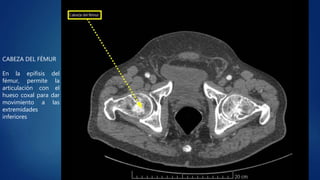

El documento describe brevemente cinco partes del cuerpo humano: el hígado, el riñón derecho, la articulación costovertebral, el hueso coxal y la cabeza del fémur. Se proporciona una función clave de cada parte del cuerpo.